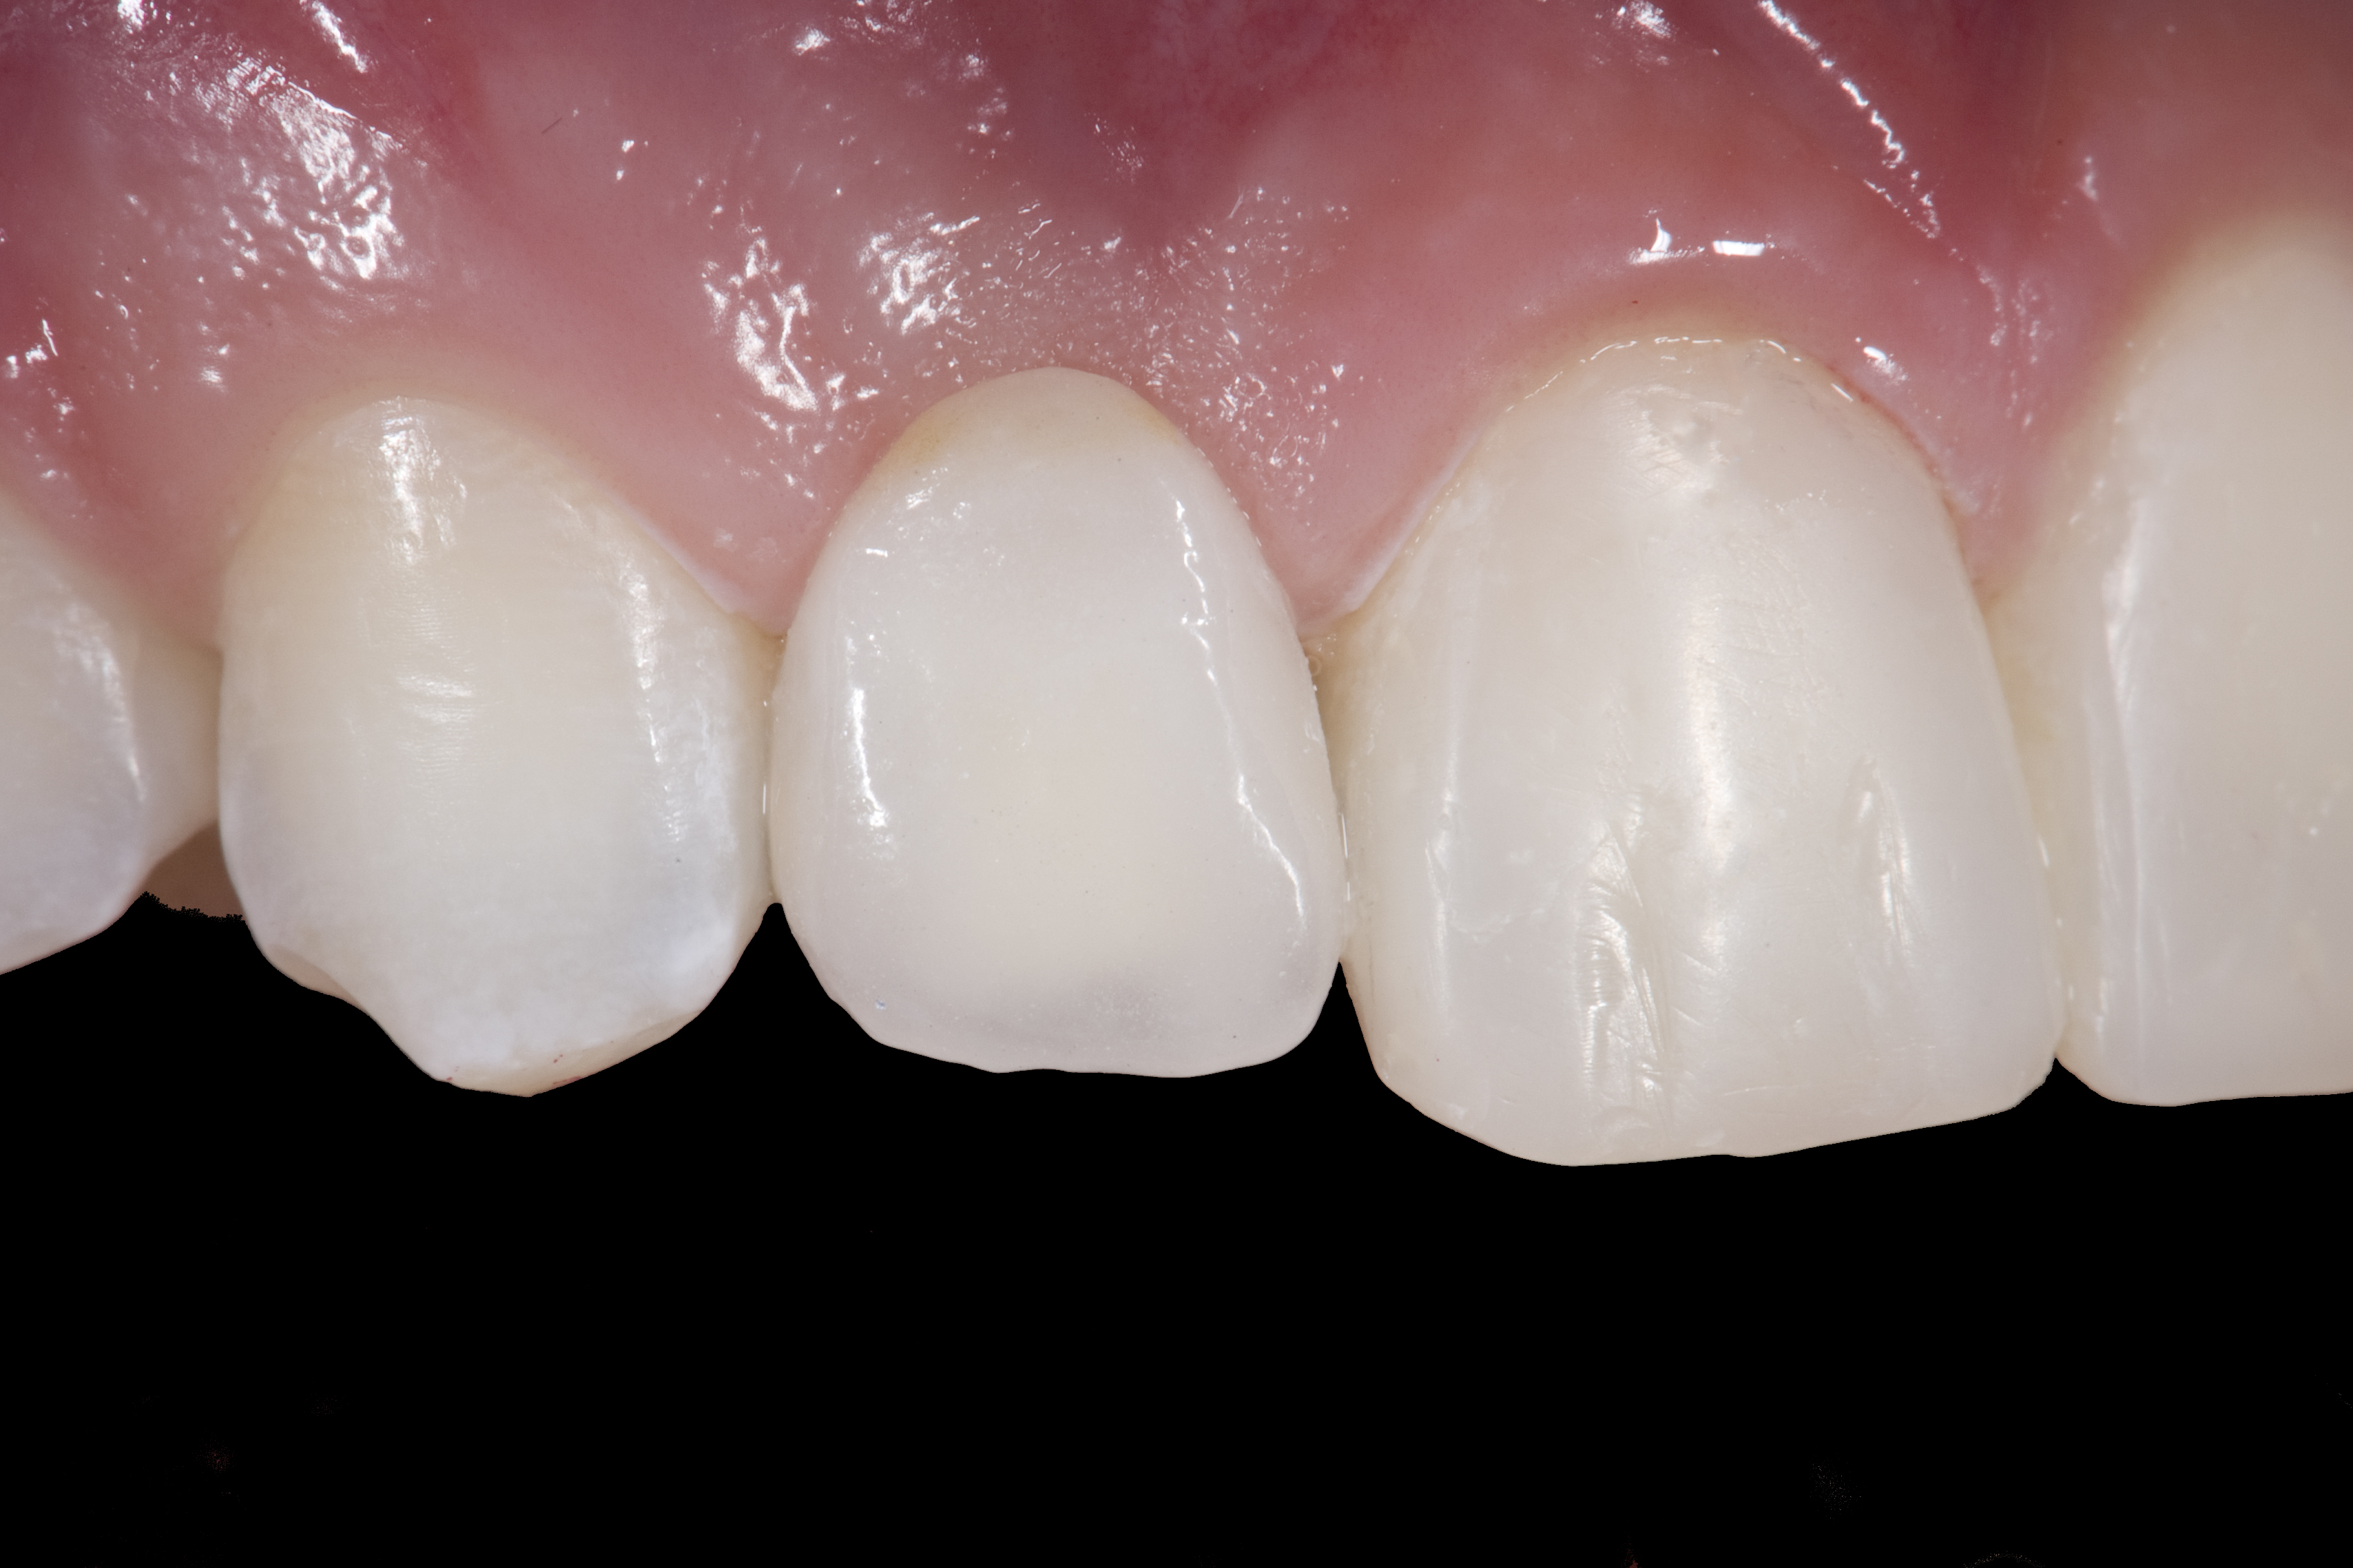

(20.) Facial view of final single-wing, modified zirconia resin-bonded bridges.

Figure 20

(21.) Smile view.

Figure 21

(22.) Right lateral view.

Figure 22

(23.) Left lateral view.

Figure 23